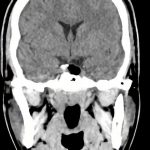

症例 '16年8月

No.

年_番号

手術年月

患者年齢

’16_127

'16年8月

20代

病名

術式

備考

下垂体腫瘍

断層撮影

手術前

1

手術前2

手術後